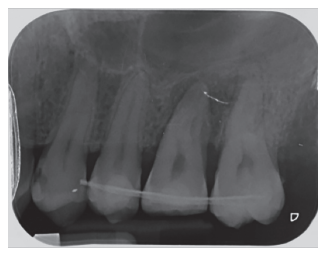

Caso clínico: se presenta el caso de un varón de 28 años, que acudió a consulta por la presencia de unos restos radiculares en localización de primer molar superior izquierdo. Se realizó un autotrasplante dental, siendo el diente donante el tercer molar superior izquierdo, que se trasplantó al alveolo del primer molar, mostrando buena evolución clínica y radiográfi ca.

Clinical case: a clinical case of a 28-yearold man is presented, who went to dental clinic for removal of left fi rst molar roots. An autotransplant was performed using left third molar as donor tooth, which was transplanted into fi rst molar alveolus, showing promising clinical and radiographic evolution.